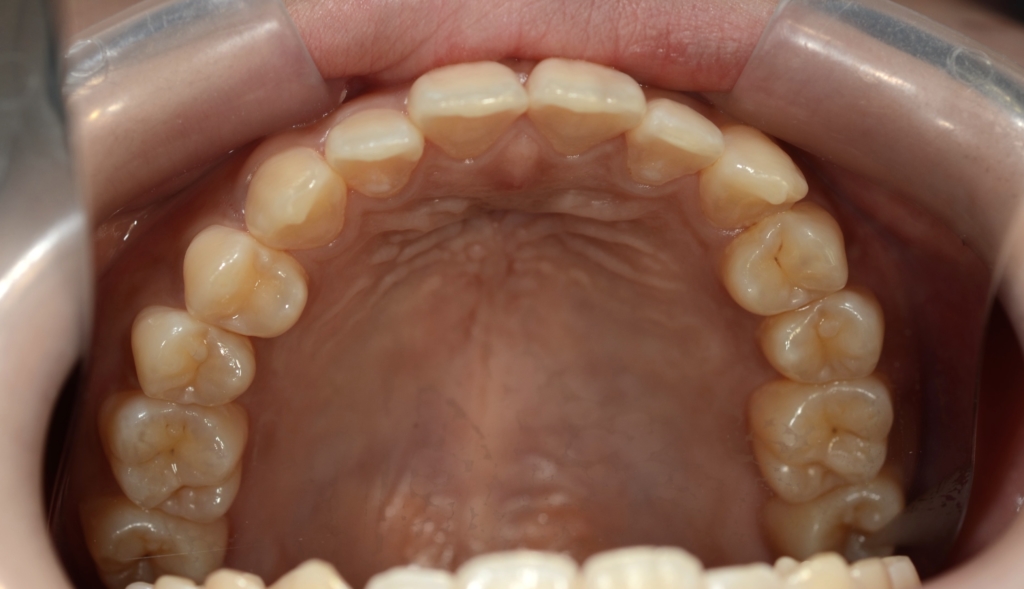

【診断】

#1.上下顎前突

(噛み合わせは上顎前突傾向)

#2.歯と顎の不調和による(軽度の)叢生

【治療方針】

1.上下左右の奥歯を1本ずつ抜歯してスペースを作り、前歯の軽度の乱れを改善

2.残りのスペース分を使い、上下前歯を最大限に後方へ移動

3.アンカースクリューを用いて上の歯列全体を更に後方へ移動させる

という治療計画にて、矯正を進めることにしました。